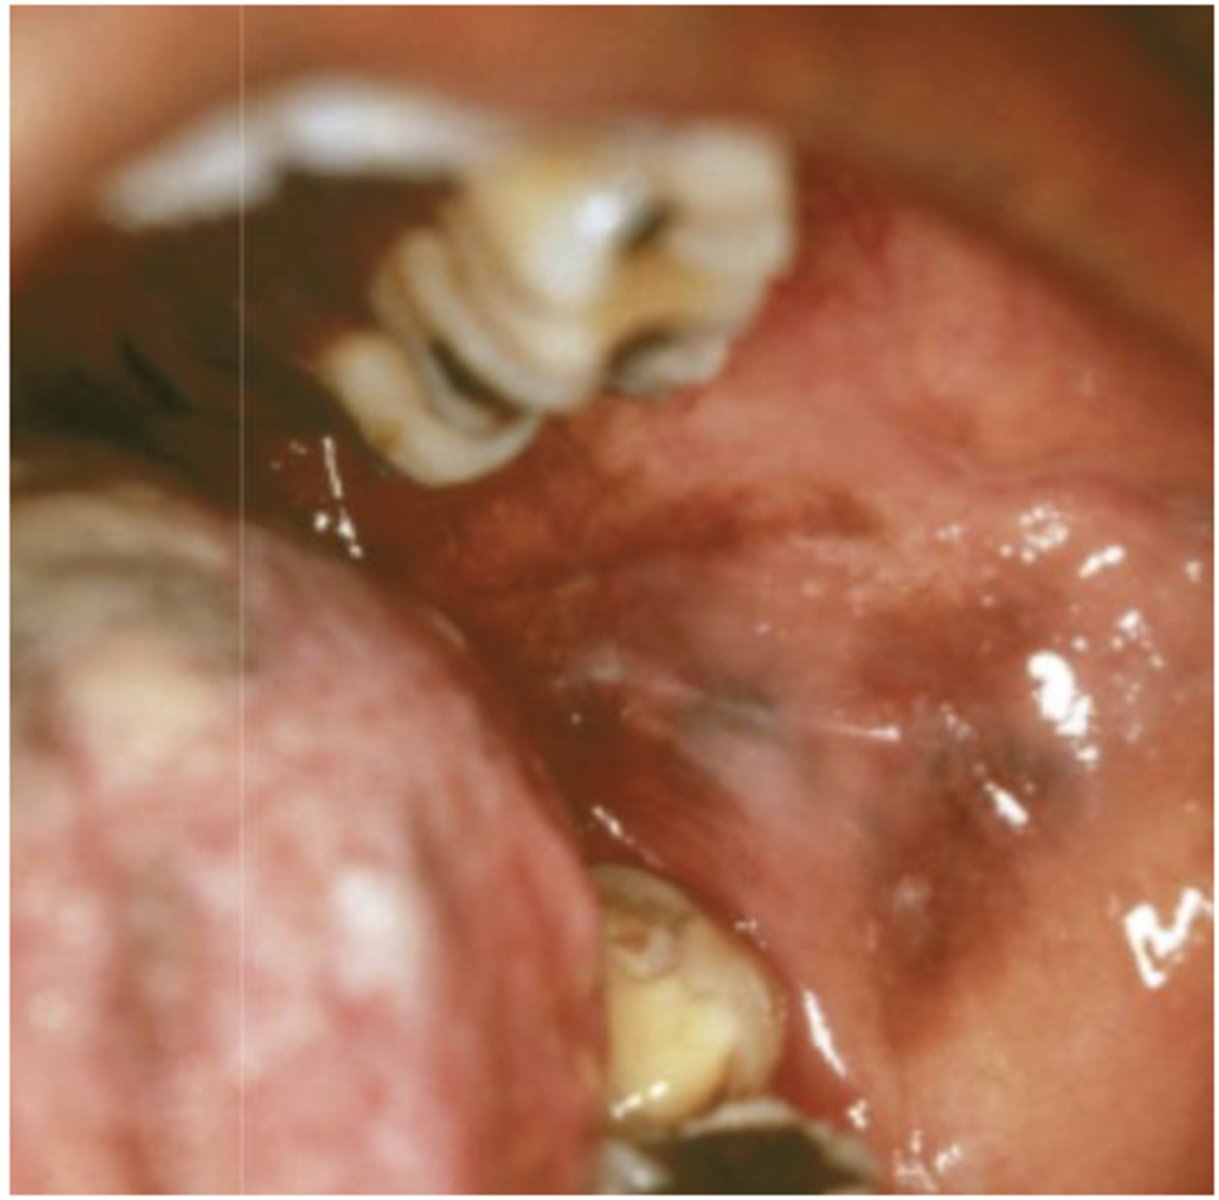

What type of pigmented lesion?

post inflammatory hyperpigmentation

- Post-inflammatory hyperpigmentation

- Facial gingiva affected most often

- May be seen in 20% of smokers

smoker's melanosis

Patient is a smoker. What type of pigmented lesion?